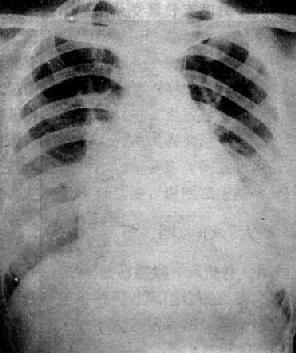

图3-2-21 房间隔缺损

右前斜位:右心室增大,肺动脉段突出,心前间隙变窄,无左心房增大后前位:心增大,呈二尖瓣型,右心房及右心室增大,肺动脉段突出,肺纹理增强左前斜位:右心房及右心室增大,左心室被增大的右心室推向后